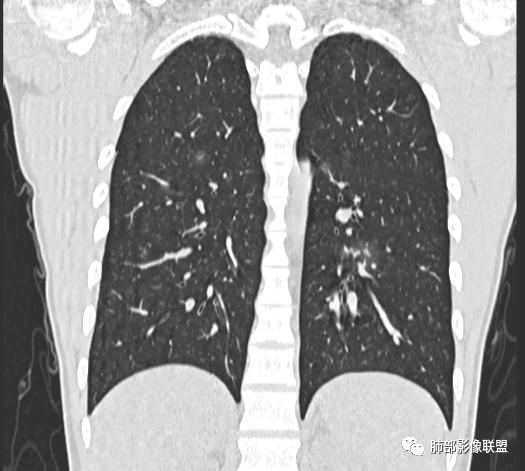

男,19岁

主  诉:发热、全身皮疹2天。

现病史:患者源于2天前受凉后出现发热,最高体温为38.5℃,且颜面部出现少量皮疹,无鼻塞、流涕、咳嗽、咳痰,未在意而未作特殊处理,次日全身皮疹逐渐增多至全身,伴轻度瘙痒,在当地卫生所给予抗病毒、抗感染治疗(具体用药不详)体温有所下降,但皮疹无明显消退,无腹痛、头痛,食欲无明显减退,为进一步诊治,遂于今日急来我院求治,患者目前精神尚可,体力正常,食欲正常,睡眠正常,体重无明显变化,大便正常,排尿正常。

小强:青年,发热,皮疹;双肺散在结节,周围磨玻璃,点晕征,疱疹病毒感染,鉴别荚膜组织胞浆菌,结核。 大雄:青年,急性起病,发热伴全身皮疹2天,抗病毒治疗体温有下降。双肺随机分布大小不等类圆结节,“点晕征”。考虑水痘-疱疹病毒(VZV)血播询问接触史,查体皮疹分布以及形态基本可诊断。 王开金江津中心医院呼吸科:青年男性,起病急,病程短,以发热,皮疹为首发症状,感染指标以单核细胞升高为主,胸部ct双肺多发结界,周围有晕,点晕表现,随机分布,同意於老师意见,水痘疱疹病毒血流感染累及肺。 王秀仙:双肺多发大小不等结节,周围有晕,边缘模糊,呈点晕征表现。青年,急性起病,发热伴全身皮疹2天,抗病毒治疗体温有下降。考虑疱疹病毒。鉴别荚膜组织胞浆菌。 傅昌瑜:19岁男性,发热、全身皮疹2天,单核细胞增高,双肺多发结节,结节边缘见边界不清磨玻璃影。点晕征+发热、全身皮疹+单核细胞增高——考虑水痘-带状疱疹病毒肺炎。 一切∮随缘:年轻男性,发热,皮疹两天,实验室,CRP,PCT增高,影像:双肺多发散在磨玻璃结节,边界欠清,大小不等,呈点晕征改变,以血管束周围分布为主,局部血管束略增粗,其它无明显改变,考虑:1:病毒性肺炎(水痘疱疹病毒?不知道皮肤有无改变)2:真菌(组织胞浆菌,血管侵袭性肺曲霉)3:GPA4:寄生虫(实验室没有看到嗜酸细胞增高) 赵山河:双肺散在结节,周围有晕,边缘模糊,呈点晕征表现。青年,急性起病,发热伴全身皮疹2天,抗病毒治疗体温有下降。考虑水痘—疱疹病毒感染。洪桥爱:青年男性,发热、皮疹2天,伴瘙痒,皮疹于面部首发,之后进展至全身,虽然没有对皮疹进行描述,但是从出疹时间及皮疹进展情况,伴瘙痒,应该就是个水痘患者;CT提示双肺随机分布结节影,部分结节伴有边界不清晕征,考虑水痘血播肺。 刘强:年轻男性,急性起病,皮疹,发热,抗感染治疗体温下降,说明有效。影像表现为散在点晕征,感染类疾病谱(疱疹病毒,真菌,结核),结合年龄,皮肤皮疹,考虑水痘-疱疹病毒性肺炎。 小兜:男性,19岁,发热皮疹两天,颜面部至全身,CRP,降钙素及单核增高。CT示双肺散在小结节,周围伴磨玻璃影,点晕征,考虑为水痘-带状疱疹病毒(varicella-zoster virus,VZV)肺炎 必有路:青年,皮疹+发热+“点晕征”→水痘-疱疹病毒(VZV) 许慧良:青年男性患者,发热、皮疹2天,体温最高38.5℃,第3天皮疹扩展至全身,伴瘙痒,胸部CT:双肺多发随机分布的小结节,结节周边见边界模糊的晕征,考虑水痘病毒感染流心明智:男,19,急性起病,发热伴全身皮疹2天。出疹顺序头→全身,抗病毒有效。胸部CT:两肺多发大小不等类圆形实性小结节影,随机分布,结节周围环绕GGO,边界模糊,呈点晕征。出疹特点是关键,未提示。考虑:血播病毒性肺炎,水痘-疱疹病毒?麻疹?鉴别荚膜组织胞浆菌、TB、血管炎、寄生虫等。 浪迹天涯:病灶多为5-10mm大小结节,结节周围可见磨玻璃样的晕环,常多发,可分布于肺内任何区域,考虑水痘—带状疱疹病肺炎如果短时间内有新的一个区域浸润,更加能说明,